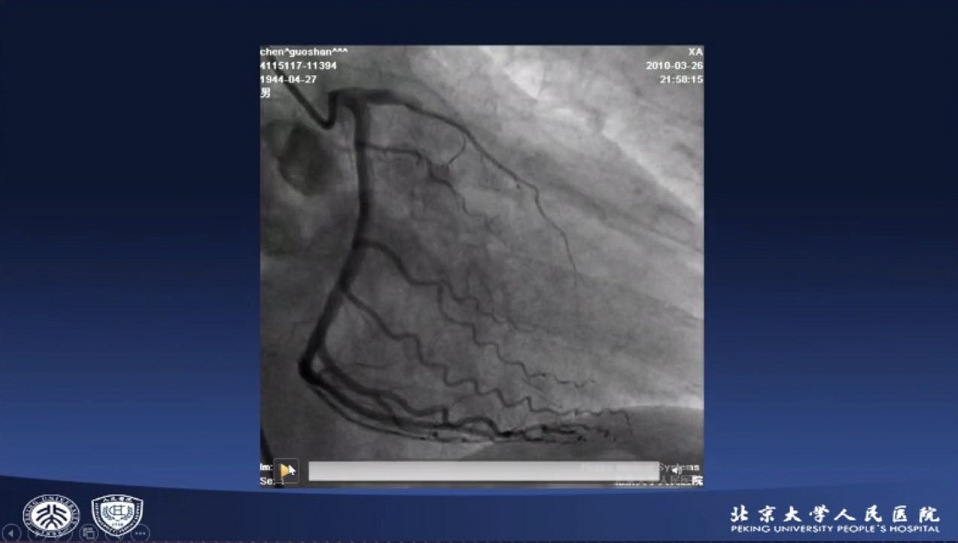

患者为69岁男性,以“突发胸痛2小时”入院,心电图示II、III、aVF导联ST段抬高,Q波形成,考虑急性下后壁心肌梗死。行急诊冠脉造影,LAD近中段弥漫性重度狭窄;LCX可见钙化斑块;RCA近中段原支架通畅,远端可见大量血栓,TIMI血流2-3级。

图片

基于现有证据及专家共识,赵博教授使用Thrombuster II抽吸导管对RCA远段病变进行TA,复查冠脉造影仍有慢血流,遂在体外将抽吸导管冲洗干净后反复进行TA,同时经抽吸导管予以替罗非班及硝酸甘油,行OCT评估可见斑块破裂及管腔内血栓残留。随后于病变处植入3.0*30mm Resolute支架,并使用3.25*12mm、3.5*12mm Quantum球囊后扩张,患者血流明显改善,复查造影及OCT结果满意,结束手术。术后1年随访患者无心绞痛复发。

赵博教授认为,TA适用于血栓负荷重的ACS、支架内血栓、无复流/慢血流这些情况。行TA时要选择支撑力强的指引导管,若病变通过性较差,可以先使用小球囊进行预扩张。同时要注意的是,若术中要经抽吸导管给药,切记要先在体外将抽吸导管冲洗干净,确保无血栓或异物残留。

郭金成教授结合这一病例讲道,目前高血栓负荷的定义仍是基于冠脉造影,尚无腔内影像学相关定义。但是腔内影像学可以测量血栓体积,评价TA效果更为准确。对高血栓负荷患者行TA是很合理的,但需要注意,直径2.0mm以下的小血管则不建议TA。